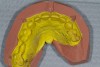

Figure 5  Laboratory alteration of the gingival contours in diagnostic wax-up.

Figure 5